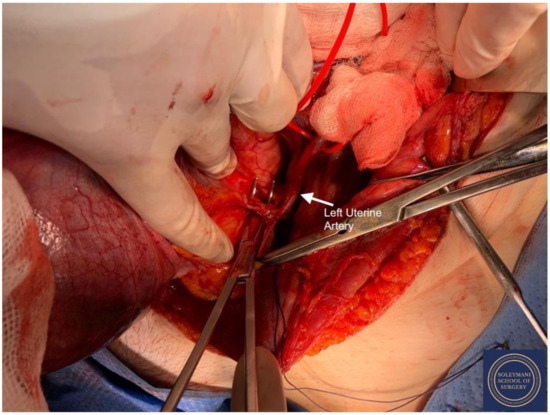

Approach to Radical Hysterectomy for Cervical Cancer in Pregnancy: Surgical Pathway and Ethical Considerations

by Rocco Guerrisi, Sarah Louise Smyth, Lamiese Ismail, Amanda Horne, Federico Ferrari and Hooman Soleymani majd

J. Clin. Med. 2022, 11(24), 7352; https://doi.org/10.3390/jcm11247352 - 10 Dec 2022

Introduction. Cervical cancer is currently the fourth most common cancer in women and in the poorest countries this neoplasia still represents a widespread and potentially lethal disease. We present a rare case of cervical cancer in pregnancy, analyzing the historical changes behind the procedure of radical hysterectomy for cervical cancer and discussing variations in surgical techniques and anatomical definitions that have since been proposed. Results. We present the case of a 33-year-old patient who attended with vaginal bleeding in the second trimester of pregnancy. Examination revealed an abnormal looking cervix, with investigations concluding stage IIb squamous cell carcinoma. Following extensive discussion regarding management options, the patient went on to have a peripartum foetocidal type III nerve sparing radical Wertheim hysterectomy at 18 weeks gestation with conservation and transposition of the ovaries above the level of the pelvic brim. The patient recovered well without significant morbidity and received further input from fertility and psychological medical teams in addition to adjuvant treatment within the department of clinical oncology. Discussion. This case represents several elements of great interest and learning. Notably, we highlight this both due to the surgical challenges that a gravid uterus presents in the execution of a radical hysterectomy; and regarding the compassionate care demonstrated by the team - not only in supporting the patient and her partner in a period of profound turmoil in terms of the management of their cancer diagnosis and unborn child, but also regarding the uncertainty in consideration of the oncological and fertility related outcomes. Conclusion. This manuscript adds to the growing literature on the appropriate use of radical surgery for cervical cancer, more specifically during pregnancy and in consideration of such ethical dilemma, where management guidelines do not exist to aid clinicians further in their provision of treatment. Full article